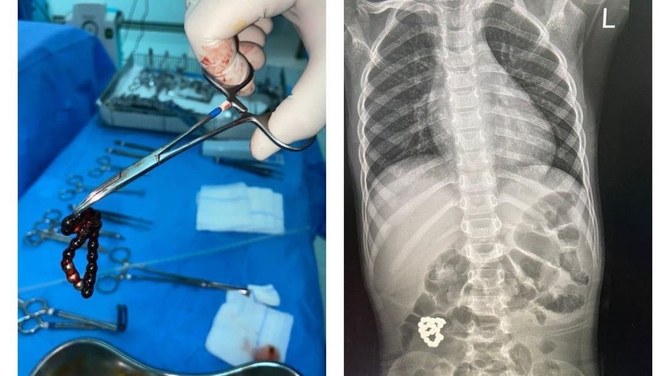

أظهرت فحوصات الأشعة السينية لجسم الطفل سوارًا في أمعائه، وفقًا لتقرير قناة العربية.

أجرى فريق طبي من الأخصائيين بمستشفى الملك عبد العزيز بجدة عملية جراحية استغرقت ساعتين ونصف لإنقاذ الطفل الذي نقل إلى المستشفى قبل أيام قليلة بعد إصابته بألم شديد في معدته.

بوابة أوكرانيا -كييف- 30 ديسمبر 2021 -تمكن فريق من الأطباء من استخراج سوار يحتمل أن يكون خطيراً من معدة طفل سعودي يبلغ من العمر ست سنوات.